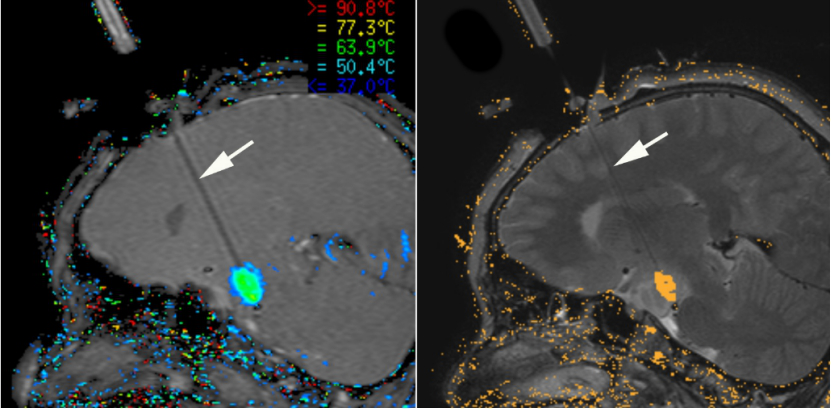

LIT是一种微创治疗方法,它使用细激光光纤(Arrow)在实时磁共振成像的引导下精确地损害肿瘤组织。

在手术过程中,实时核磁共振成像会生成病人大脑的实时温度图。这使得外科医生可以持续监测脑组织的温度,以确保激光诱导的损伤合适地瞄准肿瘤,并限制在肿瘤周围的健康组织内。